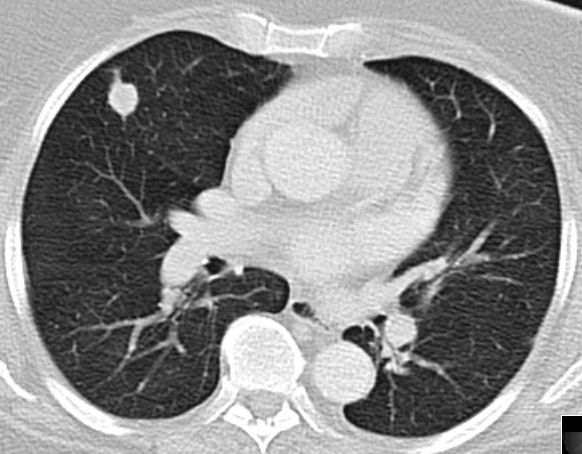

CT

61-jährige Frau mit Adipositas, Diabetes mellitus,  Hypertonie, Cholezystektomie. Vor 2 Jahren Vulva-Karzinom pT1b pN1b (1/24) M0 G2 . Vulvektomie rechts, Hemivulvektomie links mit, Sentinel-Lymphonodektomie inguinal bds. Vor 4 Monaten Lymphknotenmetastase links, R2 - Resektion, Bestrahlung abgelehnt. Jetzt progrediente Leistenmetastasierung.

Lungenmetastasen